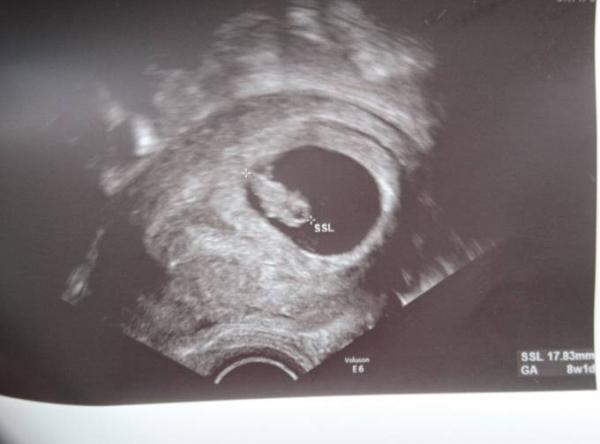

Ich traue mich bei all den schlechten Nachrichten kaum, das zu schreiben. Aber bei mir war heute alles ok. Das Krümelchen ist zeitgerecht entwickelt und schon ein richtiges, kleines Gummibärchen. Nun habe ich auch einen offiziellen ET: 14.4.20 In drei Wochen will sie noch mal gucken, dann werden wir auch entscheiden, ob wir vielleicht einen Nipt machen lassen, aber erstmal sieht sie keine Veranlassung...

Bild zu Heutiger Termin - Forum für April - Mamis